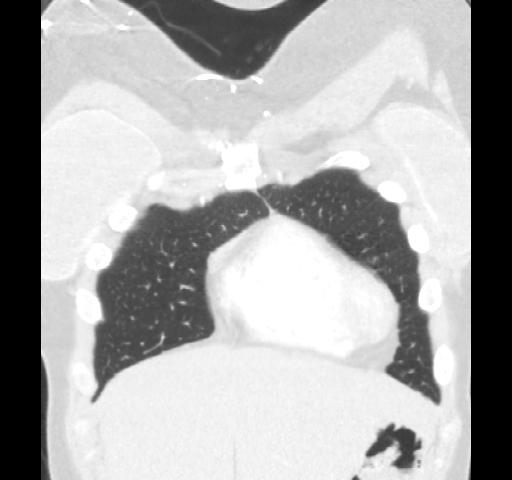

40 year old female. Breast implants 17 years ago, most likely Dow Corning. Symptoms from upper body for 6-7 years. Pain in breasts, ribs, back, neck. Skin rash. Headache and dizziness, weakness, numbness and vision disturbing. Sudden sleep episodes. Painful lymph-notes. These images are from 2010 and diagnose results were "No findings". Patient is scheduled for explantation in mid Feb. 2012